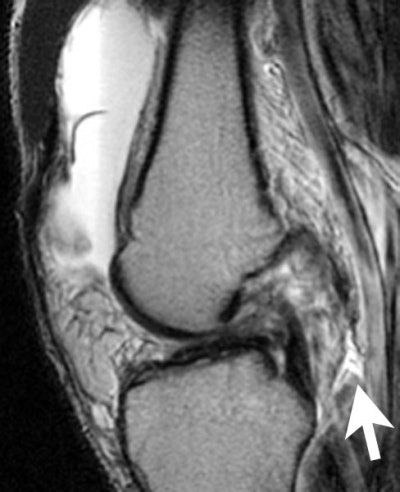

These differences in technique will be evident in a trio of sample cases. First up: The ACL-deficient knee.

Sagittal fast spin echo, T2-weighted WI with fat saturation through the chronically torn anterior cruciate ligament. As is often seen in chronic tears, the ACL has a flat course. Note the rupture of the joint capsule posteriorly (arrow), a component of the acute injury. |